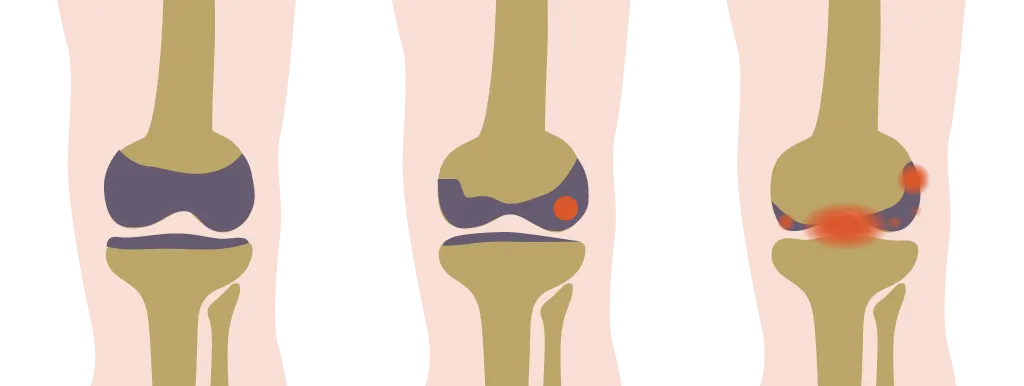

Bij MSA-patiënten verbeterden pijn, stijfheid en lichamelijk functioneren (gemeten met de WOMAC-score) eveneens significant: de score daalde gemiddeld met 8,8 punten. Daarbij verminderde het gewicht, de buikomvang en de bloeddruk. Ongeveer de helft van de deelnemers gebruikte minder pijnstillers of cholesterolverlagers. Ook hier bleven de metabole verbeteringen grotendeels intact.